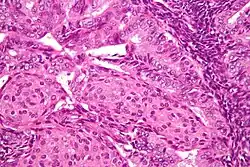

Image of the histology of an endometrial adenocarcinoma, showing many abnormal nuclei

A histologic view of an endometrial adenocarcinoma showing many abnormal nuclei

In endometrioid adenocarcinoma, the cancer cells grow in patterns reminiscent of normal endometrium, with many new glands formed from columnar epithelium with some abnormal nuclei. Low-grade endometrioid adenocarcinomas have well-differentiated cells, have not invaded the myometrium, and are seen alongside endometrial hyperplasia. The tumor's glands form very close together, without the stromal tissue that normally separates them. Higher-grade endometrioid adenocarcinomas have less well-differentiated cells, have more solid sheets of tumor cells no longer organized into glands, and are associated with an atrophied endometrium. There are several subtypes of endometrioid adenocarcinoma with similar prognoses, including villoglandular, secretory, and ciliated cell variants. There is also a subtype characterized by squamous differentiation. Some endometrioid adenocarcinomas have foci of mucinous carcinoma.[48]